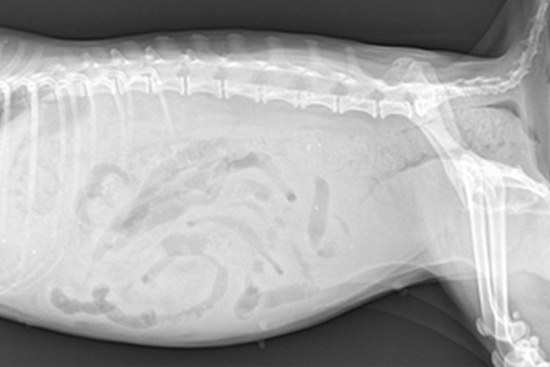

단백 소실성 장병증 (PLE, Protein losing enteropathy)

비정상적으로 장에서 단백질이 소실되는 질환을 의미합니다. 다량의 단백질이 장을 통해 소실되기 때문에 저단백혈증이 발생하게 되고 이러한 저단백혈증이 심하게 진행되는 경우에는 저알부민혈증에 의해 혈관 내 삼투압이 감소하여 흉수와 복수 등 체강 내로의 액체 저류가 발생하게 됩니다. 이러한 흉, 복수로 인해 호흡곤란, 복부팽만, 활력저하 등의 증상이 나타날 수 있으나 질환의 초기에는 뚜렷한 임상 증상이 나타나지 않을 수도 있습니다.

단백 소실성 장병증을 유발할 수 있는 원인에는 염증성 장질환 (IBD, Inflammatory bowel disease), 림프관 확장증 (Lymphangiectasia), 만성 장염, 종양 등이 있으며 저알부민혈증을 유발할 수 있는 다른 질환을 배제하고 의심되는 장에 대한 내시경 검사 또는 조직 검사 등을 통해 진단할 수 있습니다.